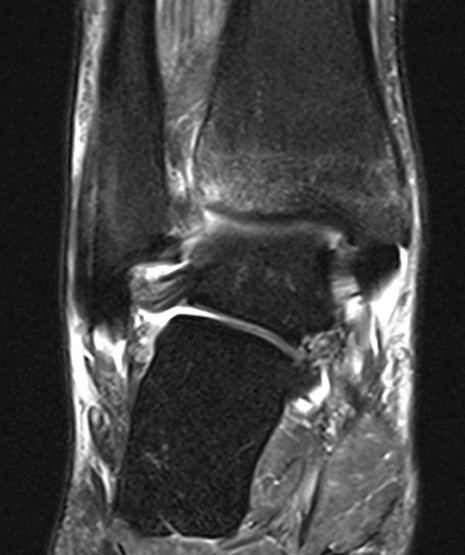

MRI

Tear of AITFL / intact PITFL

Tear of AITFL, intact PITFL, and syndesmotic injury with external rotation of the fibula

Tear of AITFL & PITFL with syndesmotic widening